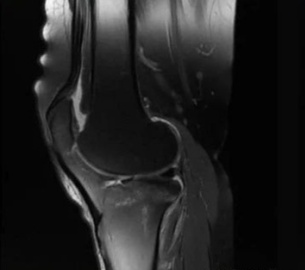

1. 磁场干扰:金属物会扭曲磁场,就像在平静的湖面扔石头,导致图像出现漩涡状伪影,重要病灶可能被完全掩盖。

2. 信号黑洞:金属会吸收无线电波,在图像上形成黑色空洞(就像照片被泼了墨水),周围组织细节全部消失。

3. 位置偏移:体内金属(如钢钉、假牙)可能轻微移位,导致图像扭曲变形,医生可能误判骨折愈合情况。